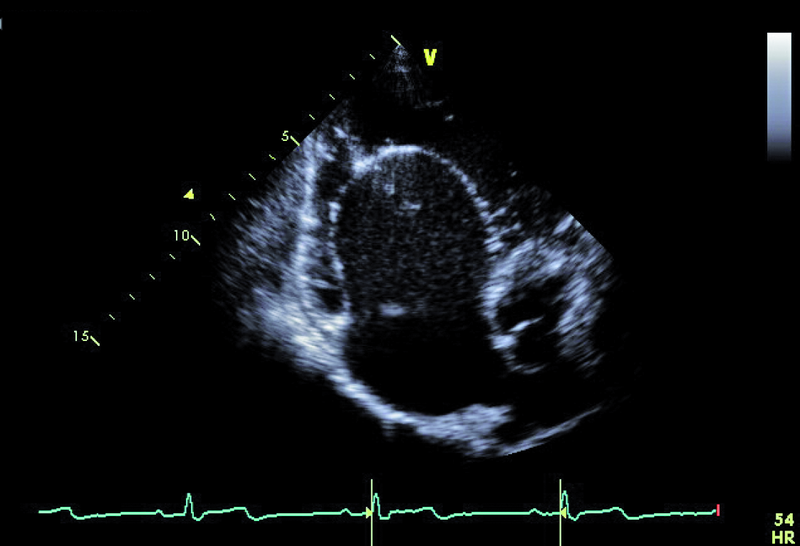

Cechy anomalii Ebsteina łatwo zidentyfikować. Należy zwrócić uwagę na odległość między przyczepem płatka przegrodowego zastawki trójdzielnej a przyczepem przedniego płatka zastawki mitralnej (ryc. 1). Fizjologiczne przesunięcie płatków jest niewielkie i zwykle nie przekracza 5-10 mm. Za kryterium rozpoznania anomalii uważa się wartość 20 mm (w przedstawionym przypadku 50 mm). Przemieszczone płatki są zwykle zmienione organicznie, pogrubiałe, często pociągane przez struny ścięgniste. Płatek przedni jest prawidłowo przyczepiony do pierścienia zastawki trójdzielnej, natomiast jest zwykle powiększony i kształtem może przypominać żagiel (ryc. 1-3). Cechą płatka przedniego w anomalii Ebsteina jest także jego nadmierna ruchomość i liczne perforacje powodujące zwykle więcej niż jedną falę zwrotną (ryc. 4). Zatrializowana część prawej komory znajduje się między przemieszczonymi przyczepami płatków przegrodowego i tylnego, a właściwa jama ma zmniejszoną pojemność. To, czy wada daje objawy, zależy od nasilenia niedomykalności trójdzielnej i od współistniejących anomalii. Niedomykalność trójdzielna u tego pacjenta, mimo dużego przemieszczenia płatka przegrodowego, była mała (ryc. 4). Zarejestrowany metodą doplerowską profil prędkości z jednego ze strumieni niedomykalności wskazywał na niepodwyższone ciśnienie w jamie prawej komory (ryc. 5). Funkcja mięśnia prawej komory określona za pomocą pomiaru przemieszczenia bocznej części pierścienia zastawki trójdzielnej była prawidłowa (ryc. 6). Diagnostykę można na tym etapie zakończyć i uznać, że chory kwalifikuje się do dalszej obserwacji. Badanie przezprzełykowe jest potrzebne u pacjentów, u których nie można ocenić dokładnie morfologii zastawki trójdzielnej. Może też być konieczne w przypadku desaturacji krwi tętniczej i podejrzenia często towarzyszącego anomalii ubytku przegrody międzyprzedsionkowej. Warto zaznaczyć, że ubytek zwykle charakteryzuje się przeciekiem prawo-lewym, na skutek dysfunkcji jam prawego serca i wzrostu ciśnienia w jamie prawego przedsionka. W tym przypadku, wobec braku sinicy, badania przezprzełykowego nie wykonano. Cewnikowanie serca także nie jest konieczne, ponieważ chory ma małą niedomykalność trójdzielną i dobrą wydolność fizyczną, a więc nie kwalifikuje się do leczenia operacyjnego.